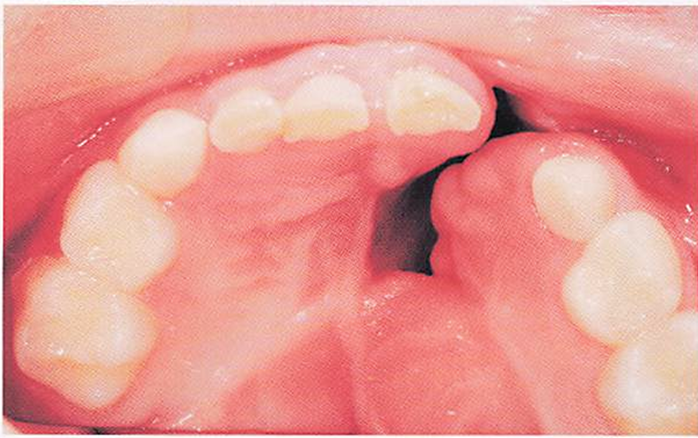

3識の男児。異常樋音があるため言語治療を受けている。口腔内写真を別に示す。考えられる構音障害の種類はどれか。1つ選べ。

a.器質性

b.機能性

c.聴覚性

d.運動障害性

解答を見る

a